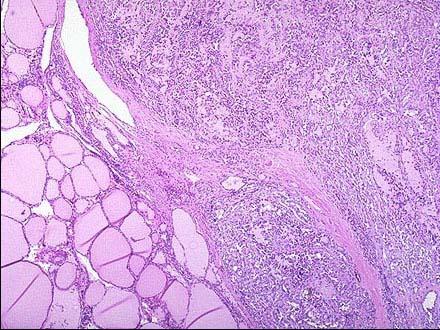

问题 图1为甲状腺髓样癌的镜下观,图2为该肿瘤刚果红染色镜下观,由此二图可知该肿瘤的哪些特征 ( )

选项 A.肿瘤间质中可见淀粉样物质沉积 B.肿瘤组织由实性细胞巢或片块构成 C.肿瘤外围可见残留的甲状腺滤泡 D.肿瘤细胞异型明显,核分裂多见 E.常见出血,坏死囊性变

答案 ABC